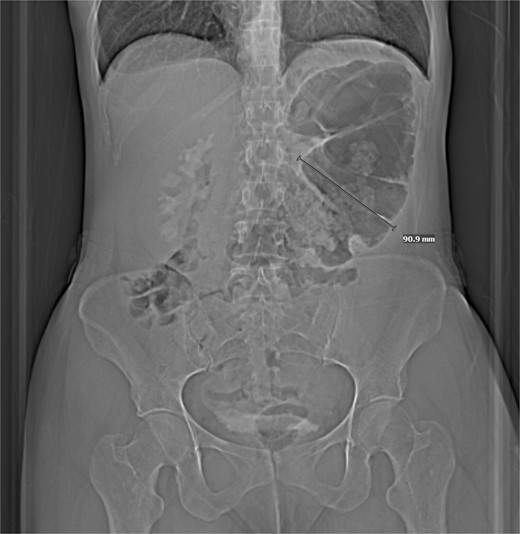

Computed tomography (CT) of the abdomen and pelvis revealed a focally dilated loop of viscera in the upper left quadrant, which was suggested to be either an internal hernia with resultant obstruction, or distention of the stomach, compatible with gastric volvulus (Fig. 1). Because of conflicting image findings, she underwent esophagogastroduodenoscopy, which was negative for gastric volvulus.

CT w/out contrast reveals focally dilated loop of transverse colon.